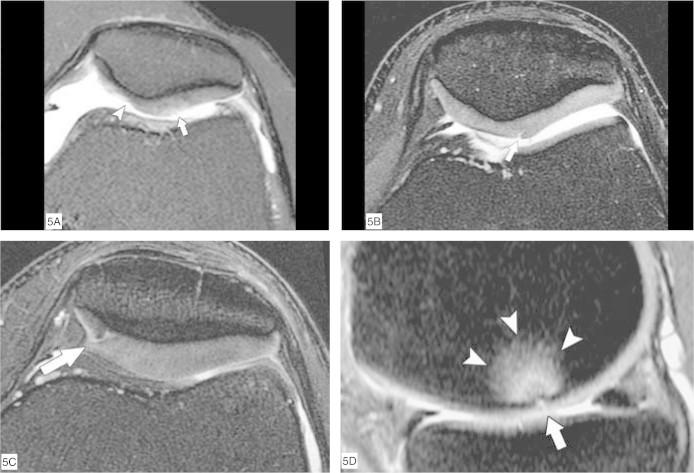

Through the ability of magnetic resonance imaging (MRI) to characterize soft tissue noninvasively, it has become an excellent method for evaluating cartilage. The development of new and faster methods allowed increased resolution and contrast in evaluating chondral structure, with greater diagnostic accuracy. In addition, physiological techniques for cartilage assessment that can detect early changes before the appearance of cracks and erosion have been developed. In this updating article, the various techniques for chondral assessment using knee MRI will be discussed and demonstrated.